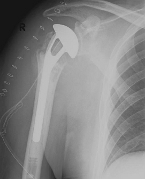

Special prostheses such as an inverse shoulder prosthesis (syn.: "Delta prosthesis", "Grammont prosthesis") for the combination of severe omarthrosis with joint instability and rotator cuff defects

Right: radiograph of an inverse shoulder prosthesis for rotator cuff defect arthropathy.

left: Inverted shoulder prosthesis (Aequalis reversed type, Tornier company).